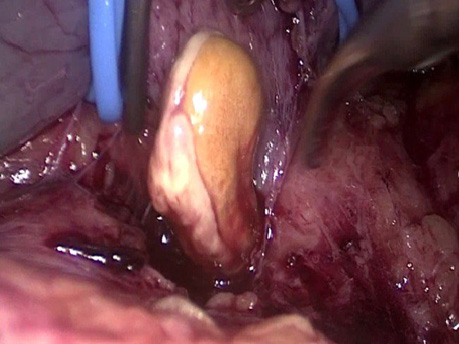

Рис. 5. Этап рассечения стенки левой почечной вены с «вывихиванием» опухолевого тромба из просвета сосуда. Верхушка опухолевого тромба (желтое)

Рис. 6. Наложение металлической клипсы на культю почечной вены

Рис. 7. Этап одномоментного рассечения и клипирования правой почечной вены с оттесненным опухолевым тромбом из нижней полой вены в просвет почечной вены

Рис. 8. Этап экстракции опухолевого тромба из нижней полой вены

Рис. 9. Этап ушивания стенки нижней полой вены после экстракции опухолевого тромба (восстановление целостности сосудистой стенки)